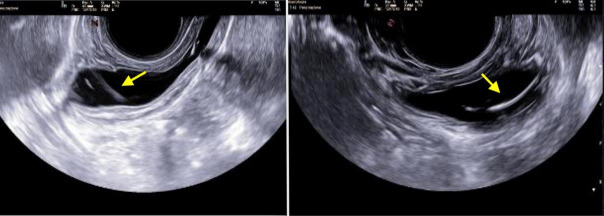

Results: The intravesical NuvaRing® was identified through pelvic ultrasound. During cystoscopy, the ring was detected inside the bladder. Multiple attempts with cystoscopic alligator graspers were made; the NuvaRing® was eventually extracted using transurethral Heiss forceps. The patient experienced minimal blood loss and was discharged the following day, reporting relief from symptoms.